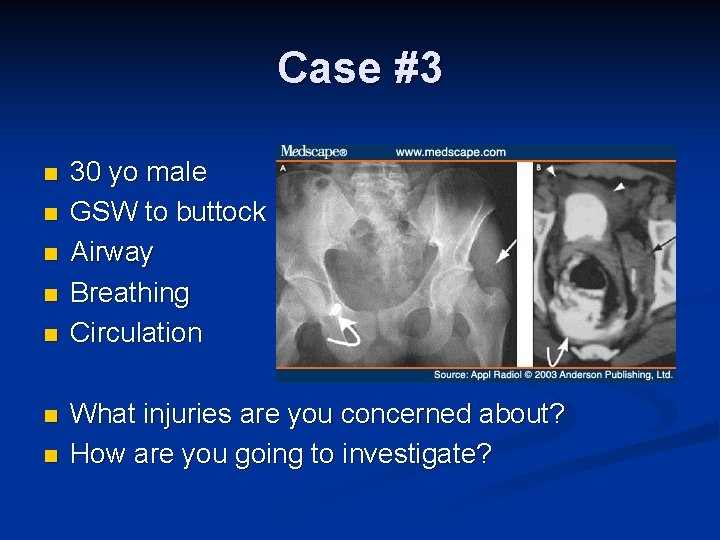

Case #3 n n n n 30 yo male GSW to buttock Airway Breathing Circulation What injuries are you concerned about? How are you going to investigate?

Transpelvic GSW n Rectal injury Extraperitoneal – rigid sigmoidoscopy n Intraperitoneal – CT scan with rectal contrast or laparotomy n n Bladder injury Hematuria n Cystogram n n Urethral injury n Retrograde urethrogram

Transpelvic GSW n Vascular injury FAST n CT Scan n n Pelvic fracture n n X-ray Female – Uterine injuries n CT Scan